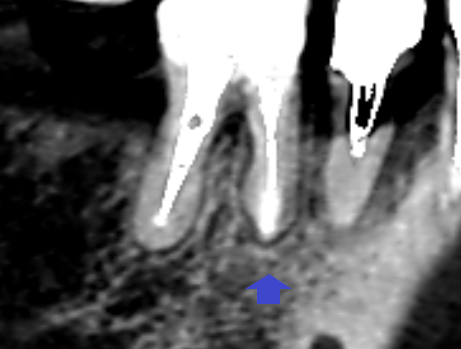

下顎第一大臼歯の精密根管治療6ヶ月後のCT画像です。矢印の先にあった、膿の影が消失し歯槽骨が再生しています。歯茎の腫れは、下顎第二大臼歯の抜歯と同時に消失したので、本ケースの歯茎の腫れは、下顎第二大臼歯の歯根破折が原因でした。